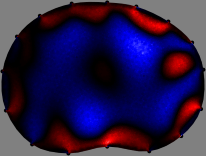

Figs. 3 and 4 compare the performance of the proposed FER method in (20) with the standard regularized least-squares method ((19) when is the identity matrix). The regularization parameter of the standard method was heuristically chosen for its best performance, and the parameter of the FER method was set to be one of three different values . The injection current was 1 mA at 100 kHz, and the frame rate was 9 frames per second. The reference frame at was obtained from the maximum expiration state. The measured data, , represent the voltage differences between each time and . The blue regions, which denote where conductivity decreased by inhaled air, increased during inspiration and decreased during expiration. The FER method with was clearly more robust than the standard method that produced more artifacts originated from the inversion process.

| Standard | |

||||||||||

| FER () | |